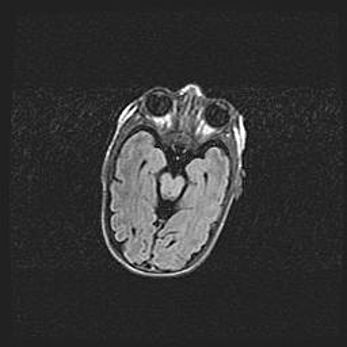

Церебральная ишемия II.

Возраст: 5 дней

Вес: 3400 г

Пол: женский

Окружность головы: 35 см

Срок гестации: 39 недель

Церебральная ишемия – это заболевание, характеризующееся недостаточностью (гипоксией) либо полным прекращением (аноксией) снабжения мозга кислородом по причине закупорки одного или нескольких сосудов. Это приводит к  что метаболическим расстройствам различной степени тяжести в тканях головного мозга, развитию коагуляционных некрозов и гибели нейронов.